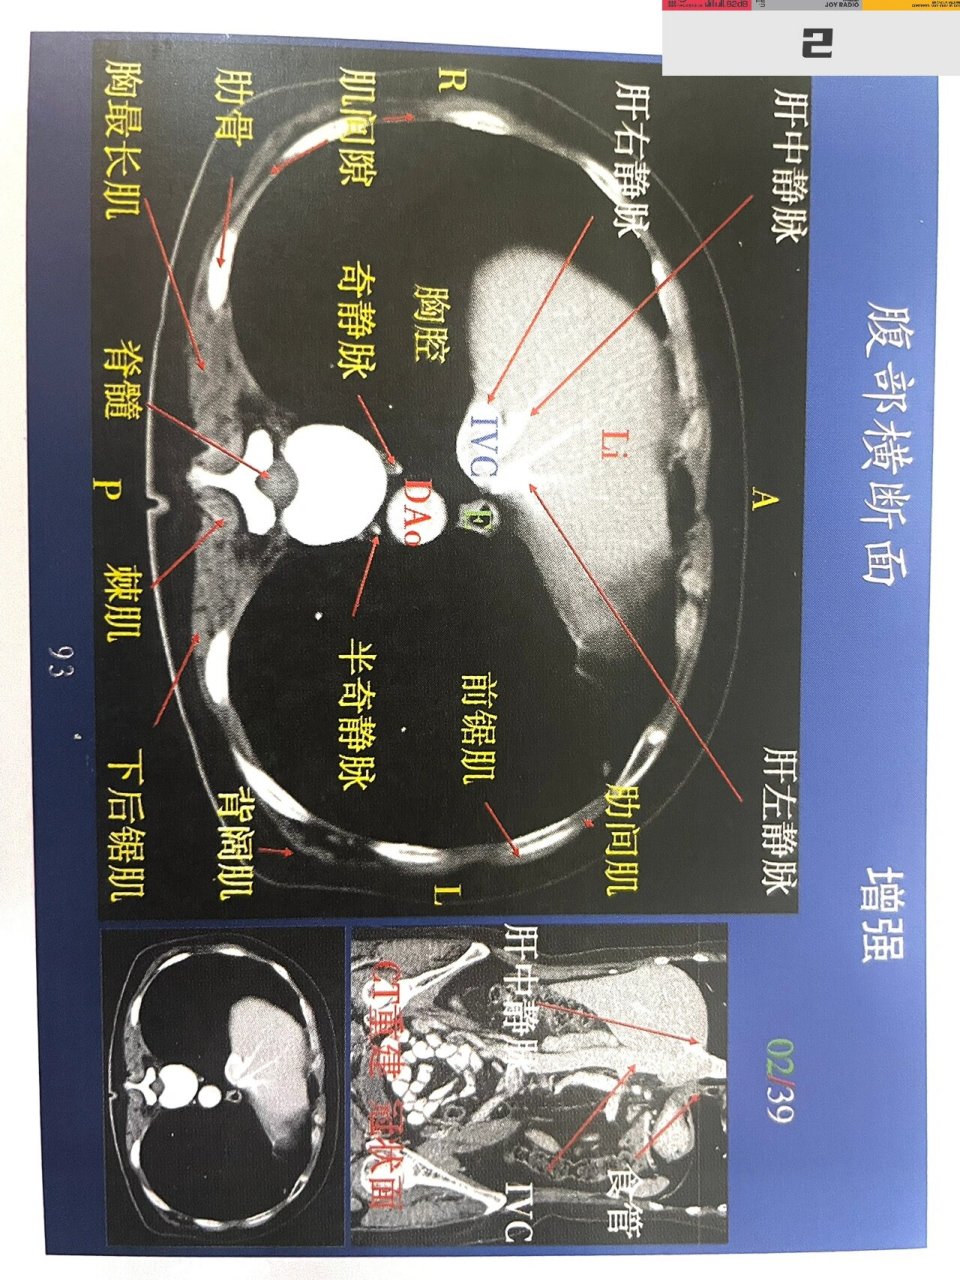

腹部第一组增强解剖!肝脏ct增强解剖!上.腹部第一组增强解剖 - 抖音

腹部第一组增强解剖!肝脏ct增强解剖!上腹部 肝脏详细横断面解剖图!